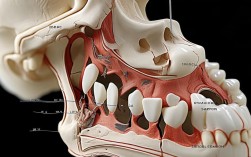

神经损伤:

- 表现: 下唇、下巴、舌头或牙龈区域出现麻木、刺痛、灼烧感或感觉异常(感觉迟钝或过敏)。

- 原因: 种植手术中,种植体植入位置过深或靠后,可能损伤下牙槽神经(下颌后牙区)或颏神经(下颌前牙区);上颌手术可能损伤鼻腭神经或上牙槽前神经。

- 发生率: 相对较低,尤其在下颌前牙区(神经位置表浅)风险略高。

- 恢复: 大多数是暂时性的(几周到几个月内恢复),少数情况下可能是永久性的(非常罕见)。

- 长期影响: 永久性神经损伤会导致该区域感觉长期异常,影响生活质量(如进食、说话、感知温度等)。

邻牙损伤:

- 表现: 相邻牙齿出现疼痛、松动、牙根吸收等。

- 原因: 术中操作不当,如备洞时产热过多、种植体植入位置不佳压迫邻牙牙根等。

- 长期影响: 可能需要额外的治疗(如根管治疗、牙周治疗,甚至拔除邻牙)。

上颌窦问题(上颌后牙区):

- 上颌窦穿通: 种植体尖端穿入上颌窦腔,可能导致鼻塞、流鼻涕、鼻腔异味、感染(上颌窦炎)。

- 上颌窦提升术并发症: 如果需要做上颌窦提升(骨量不足时),本身就有出血、感染、上颌膜穿孔、种植体进入上颌窦等风险。

- 处理: 穿通较小可能自愈或简单修补;穿通较大或感染可能需要取出种植体、抗感染治疗,甚至请耳鼻喉科会诊。

- 长期影响: 反复上颌窦炎可能需要长期治疗。